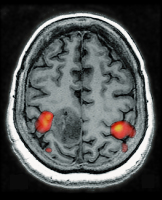

Brain tumour

Figure 1: Brain tumour localised in the primary hand motor cortex as evidenced by fMRI activation of a bilateral finger tapping task adjacent to the tumour in the precentral and post-central cortex bilaterally.

Keywords: brainfMRITumor